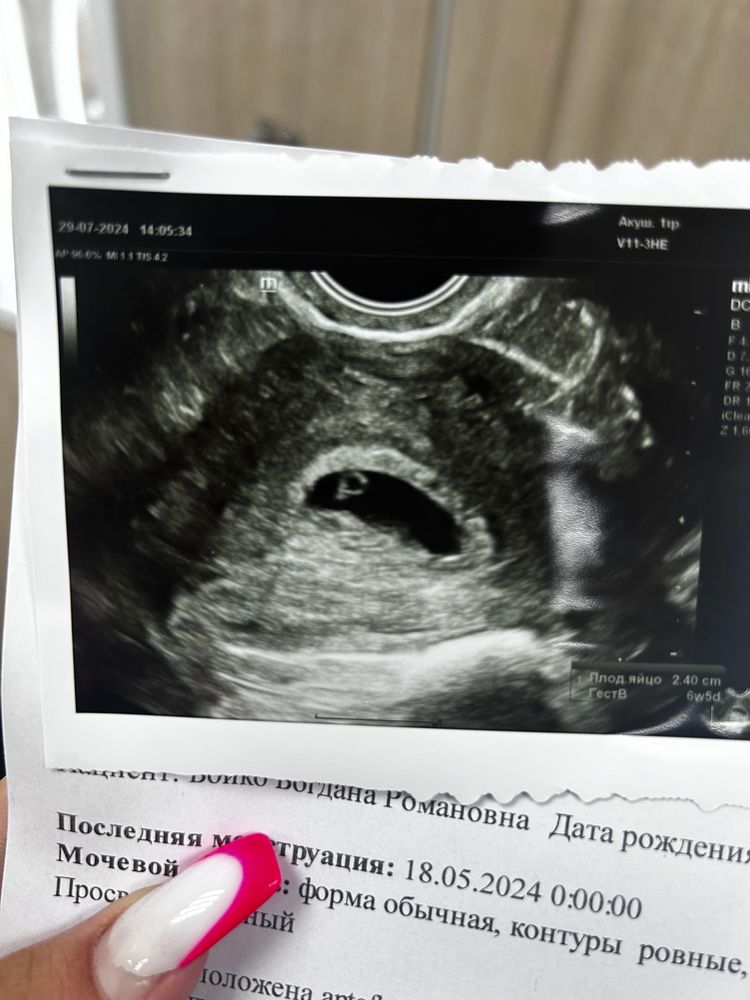

Другоевсем привет , ходила вчера на узи и во время узи немного начало кровить ( беременность примерно 5-6 недель) врач увидела небольшую отслойку нижней стенки , нашла эмбрион 2,9мм но без сердцебиения, по скорой легла в стационар, сегодня уже выделений вообще нет , укололи один раз папаверином и кровоостанавливающим , через два дня контрольное узи, как думаете есть шансы из за сбитого цикла и поздней овуляции, что сердечко забьет ?

У вас по дате последних месячных никак не может быть 5-6 недель сейчас. У вас последние месячные вы говорите были 18.05,а это уже 11 недель беременности.Вы пишите эмбрион 29 мм,это уже почти 3 см он,сердебиение должно быть обязательно уже давно на таком сроке.Если сердце на УЗИ сказали не бьётся,то тогда увы(

Или может у вас эмбрион 2.9 мм?Тогда это уже совсем может быть другое дело.

Дарья Романовна, тогда ждите и на днях делайте УЗИ,там уже станет понятно всё.У меня сердце увидели при ктр 4.9 мм.

Дарья Романовна, у вас получается овуляция-то совсем поздняя была,если месячные были аж в мае.Тогда да,срок вам будут ставить по размеру эмбриончика.Ждите,пусть сердечко появится 🙏